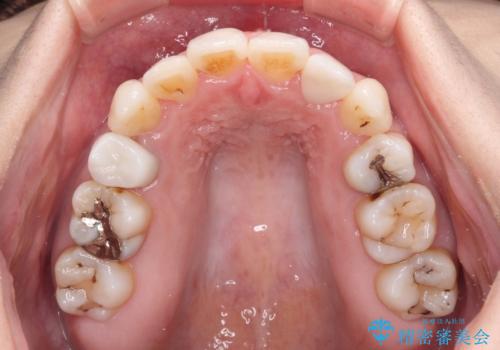

- 結婚式に向けて、八重歯と虫歯で変色した歯を改善したいとのことで来院された患者様です。

上下ともにデコボコが強いため、上下顎左右小臼歯各1歯を抜歯して歯列を整えることとしました。

大きな虫歯が認められた歯は、矯正治療後にオールセラミッククラウンにて補綴治療を行うこととしました。

抜歯矯正は、2年半程度の治療期間を要することが一般的ですが、今回はセラミッククラウンによる補綴治療も含めて2年1ヶ月で終えることができました。

元々の歯並びが思い出せないくらい、きれいに仕上げることができました。